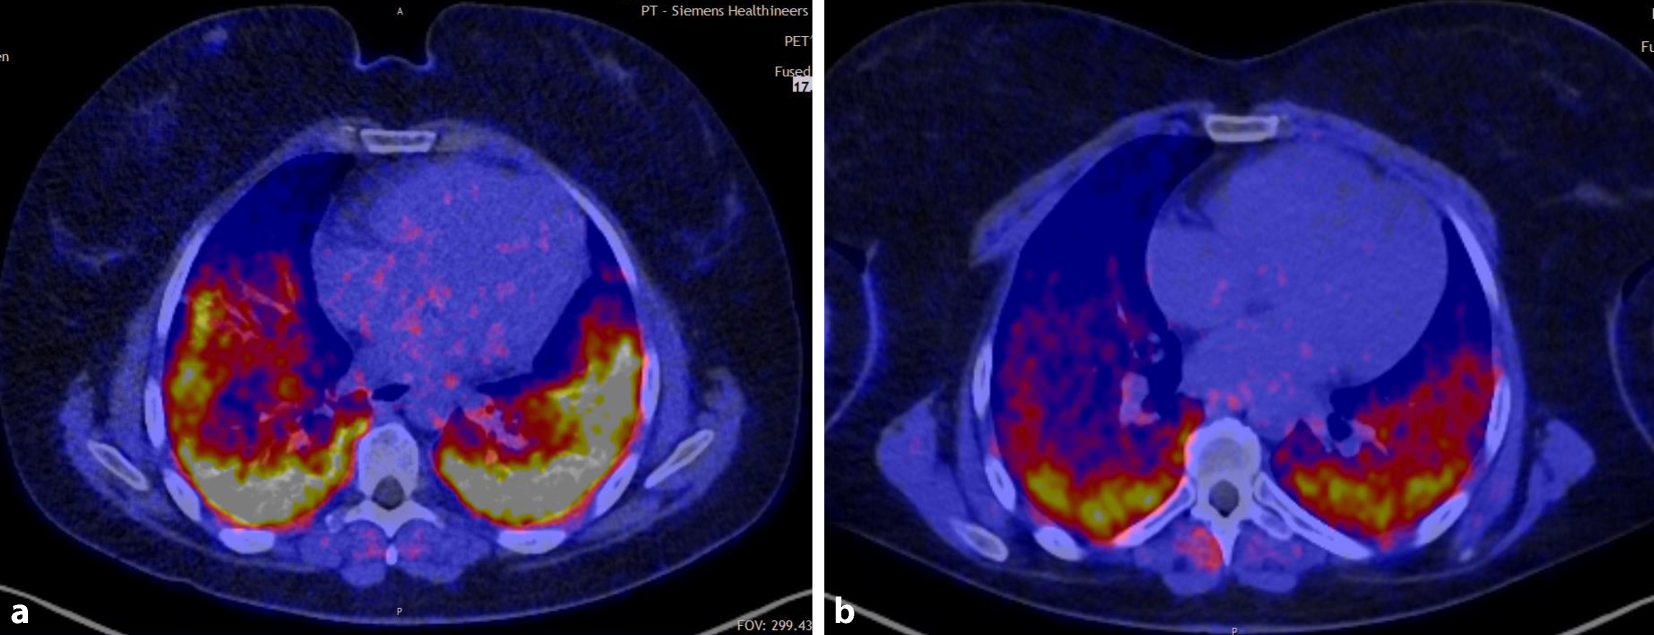

Ein weiterer Fall war eine Patientin, die ein schweres Antisynthetasesyndrom (Anti-Jo+) mit rasch progredienter Lungenbeteiligung entwickelte. Die Patientin erhielt im Mai 2022 die Erstdiagnose und war bereits 12 Wochen später sauerstoffpflichtig. Trotz intensiver Immunsuppression (Rituximab, Ocrelizumab, Cyclophosphamid) musste die Patientin High Flow-beatmet werden und war auch mit zusätzlicher Hochdosissteroidtherapie nicht kontrollierbar. Zuletzt hatte die Patientin einen Sauerstoffbedarf von 8 l in Ruhe und 12 l unter minimaler Belastung (VCmax 1,88 l). Nach erfolgreicher CAR-T-Zell-Therapie ist sie nun in therapiefreier Remission. Die Abb. 3 zeigt die Fibroblasten-Aktivierungs-Protein(FAPI)-PET/CT-Untersuchungen der Patientin vor CAR-T-Zell-Therapie und 3 Monate nach Therapie. In Ruhe benötigt die Patientin aktuell keine Sauerstofftherapie und nur minimale Therapie unter Belastung (VCmax 2,29 l).

Abb. 3

Fibroblasten-Aktivierungs-Protein(FAPI)-PET/CT-Untersuchungen vor (a) und 3 Monate nach CAR-T-Zell-Therapie (b). Der Rückgang der aktiven Entzündung des Lungenparenchyms ist deutlich. (© Med. Klinik 3, UK Erlangen)